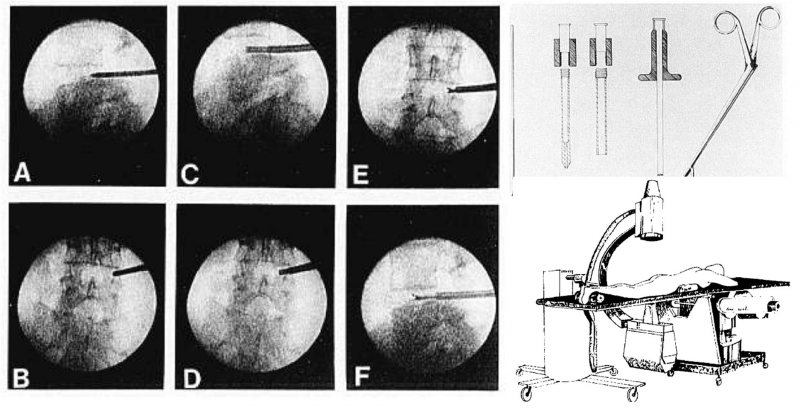

图3. Kambin发表的首篇经皮腰椎间盘切除术,术中图片、器械及手术体位。引自Percutaneous Lateral Discectomy of the Lumbar Spine A Preliminary Report. Clinical Orthopaedics and Related Research (1976-2007) 1983;174:127-132.

1986年,Schreiber和Suezawa[9]报道了使用双通道关节镜进行髓核切除术。在20世纪80年代中后期,开发了一种允许插入45°角器械的通道,但是,当时这一技术在椎间盘空间内不足以建立充足的出入水量导致视野不清,且器械活动角度有限,难以抵达后方突出间盘。直到80年代末,小直径纤维软镜出现后,Kambin开始尝试使用脊柱内镜进行髓核消融术[10],并在此后开展了许多工作[11、12],为推动脊柱内镜技术发展和传播做出了卓越的贡献。在这一阶段,单双通道均得到广泛应用。此阶段的双通道多为双侧双通道(即以脊柱为中线,在两侧建立工作通道和观察通道),用以处理包容型或中央型间盘突出等需要“持续可视化(continuous visualization)”的情况;而单通道则用于处理椎间孔区及椎间孔外间盘手术以及只需要“间断可视化(intermittent visualization)”的情况[13]。